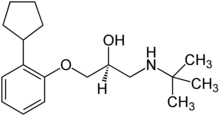

| Formula | C18H29NO2 |

| Molar mass | 291.435 g·mol−1 |

Penbutolol (brand names Levatol, Levatolol, Lobeta, Paginol, Hostabloc, Betapressin) is a medication in the class of beta blockers, used in the treatment of high blood pressure.[1] Penbutolol is able to bind to both beta-1 adrenergic receptors and beta-2 adrenergic receptors (the two subtypes), thus making it a non-selective β blocker.[2]: Table 10–2, p 252 Penbutolol is a sympathomimetic drug with properties allowing it to act as a partial agonist at β adrenergic receptors.[3]